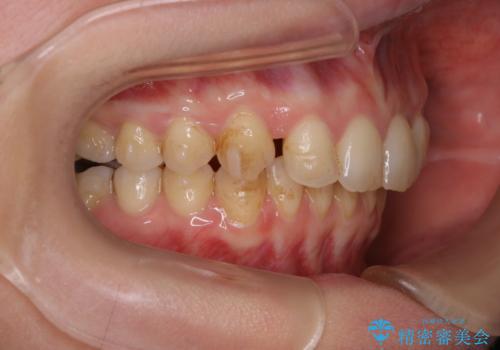

マウスピースをしたままコーヒーを飲むと着色がすごい

マウスピースをはめたままコーヒーを飲んでしまったそう。

着色がとても多くついていました。着色がここまでついていると、目立ちますし、マウスピースをはめたままのお水以外は飲むのは控えましょう。